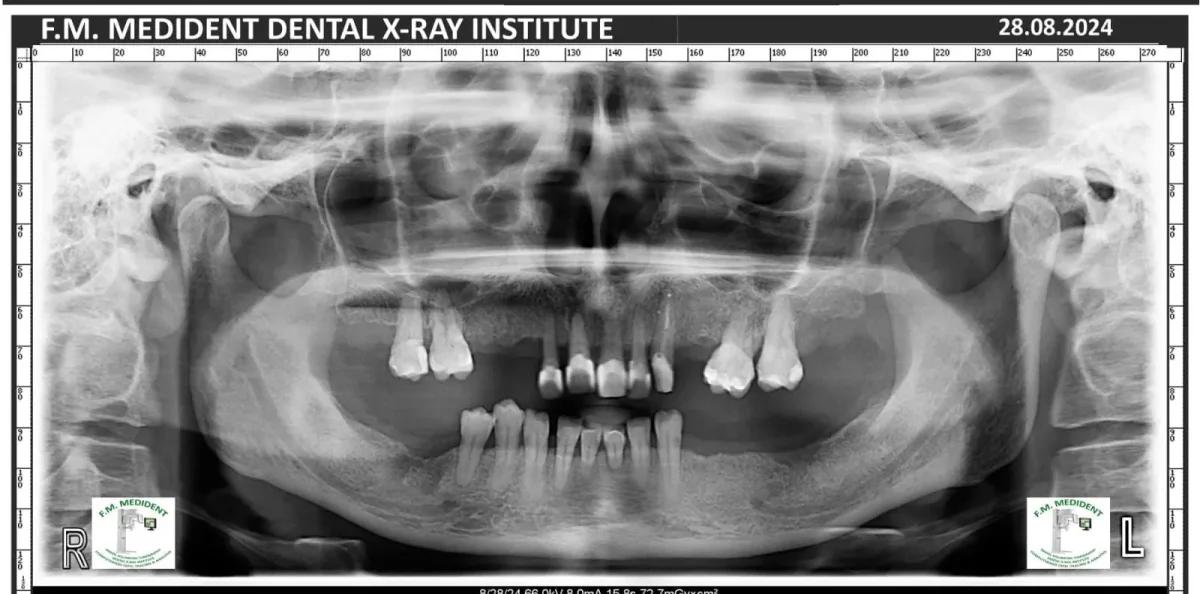

Cazuri reale înainte și după, din tratamente realizate în clinică.

Înainte

DupăExemple reale din cazuri tratate în clinică.